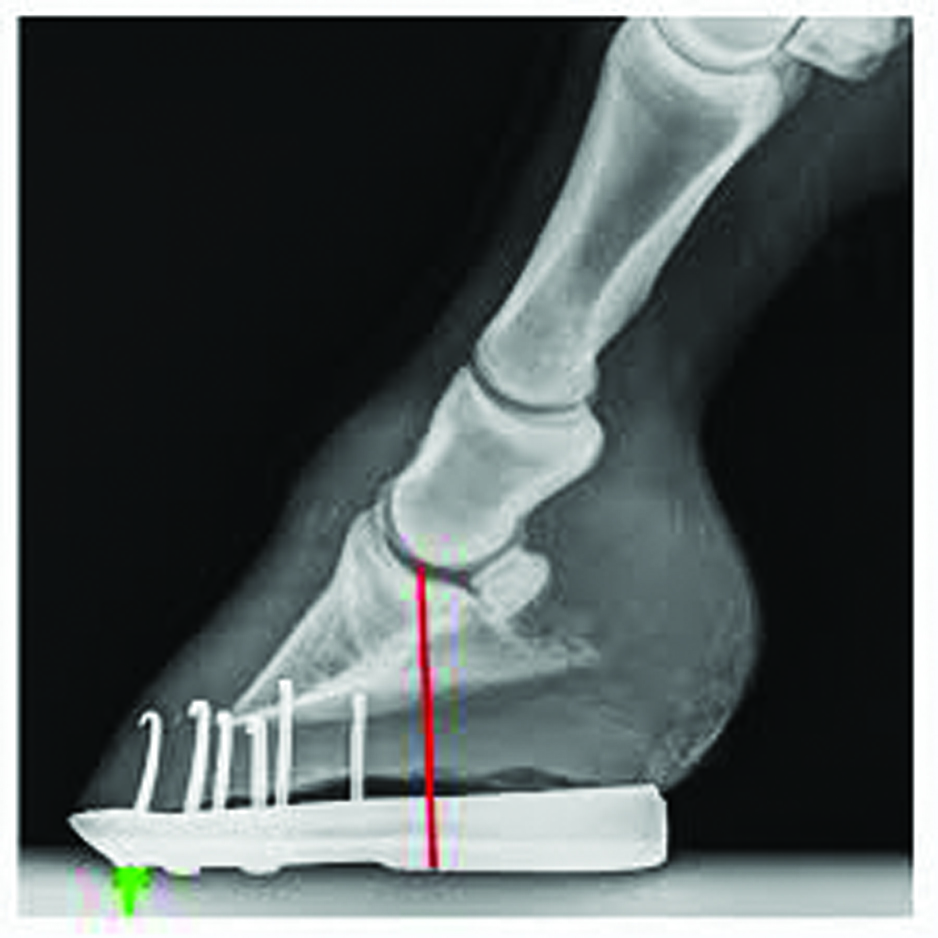

A side (lateral) view of the lower limb is very important to assess hoof/pastern angle and shoeing. This view shows placement of the shoe further forward than might be ideal.